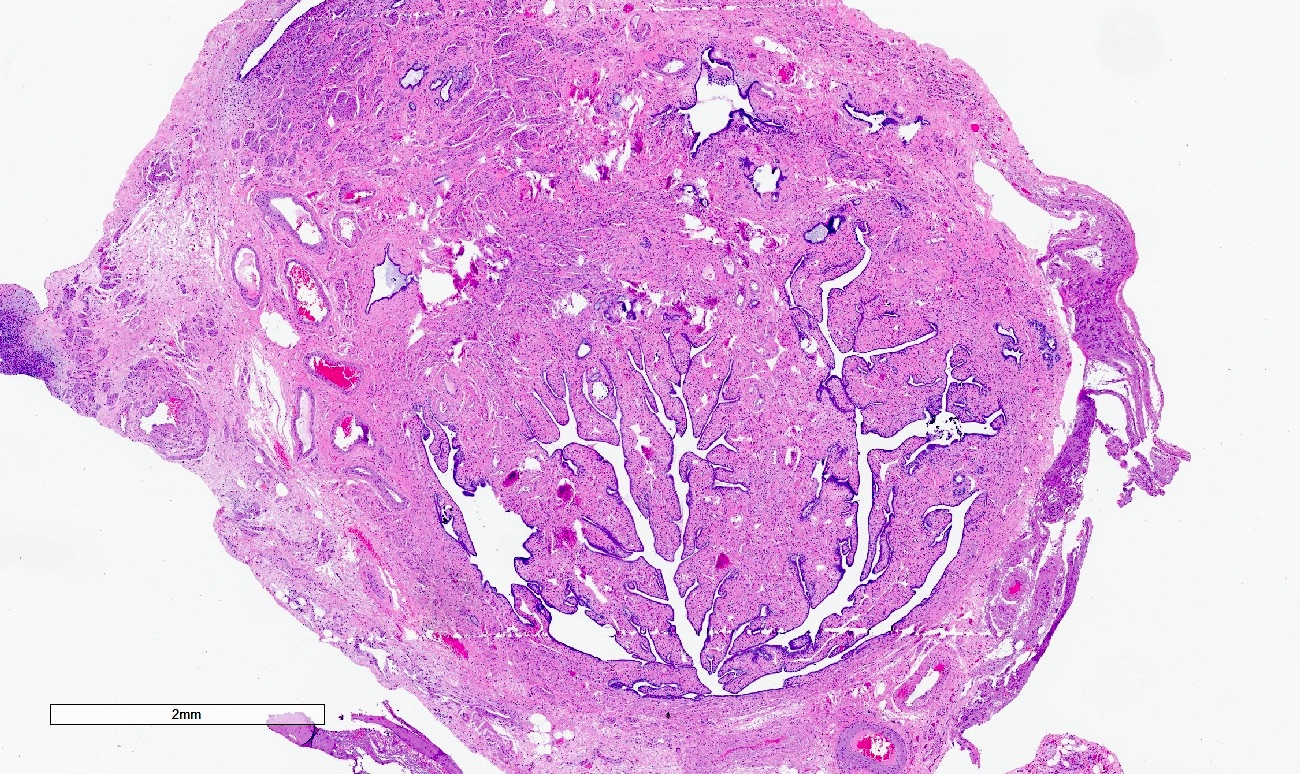

Microscopic (histologic) description

- Regularly spaced glands lined by normal appearing tubal epithelium surrounded by smooth muscle or fibrous tissue

- Tubal lumina are true diverticula that communicate with the central tubal lumen but do not connect with the serosa

- Glands can become cystically dilated (Am J Clin Pathol 1951;21:212)

- No significant atypia, scarring or associated inflammatory / stromal response

- Absence of endometrial stroma differentiates this entity from tubal endometriosis

Microscopic (histologic) images